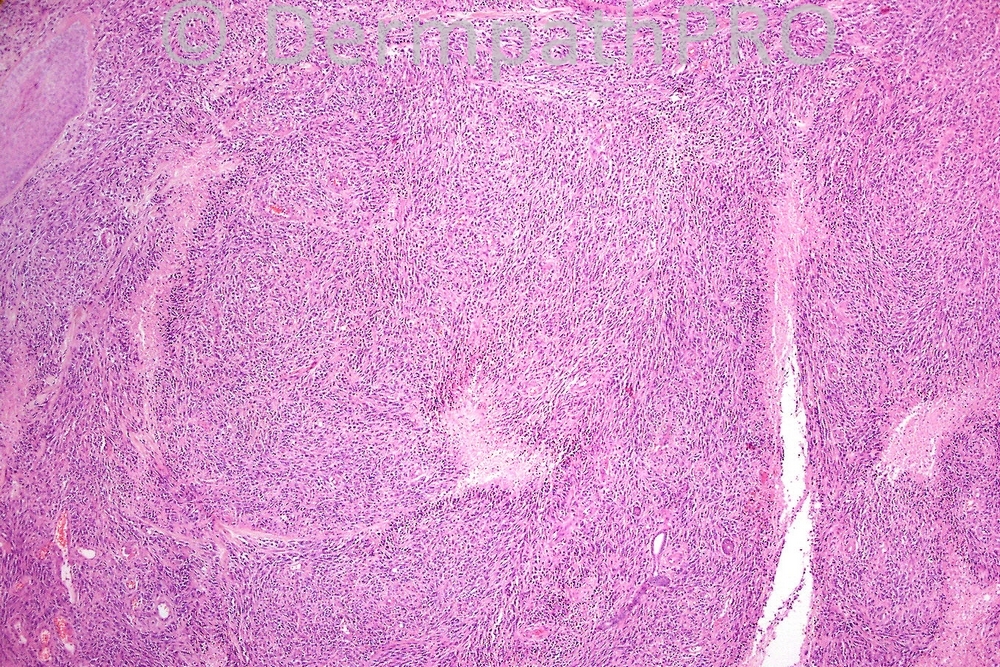

Female 86, ulcerated nodule on scalp.

Obviously immunohistochemistry is critical although in Fig 4 I tried to illustrate an intracytoplasmic lumen. The tumor expressed vascular makers and is a spindle cell angiosarcoma.